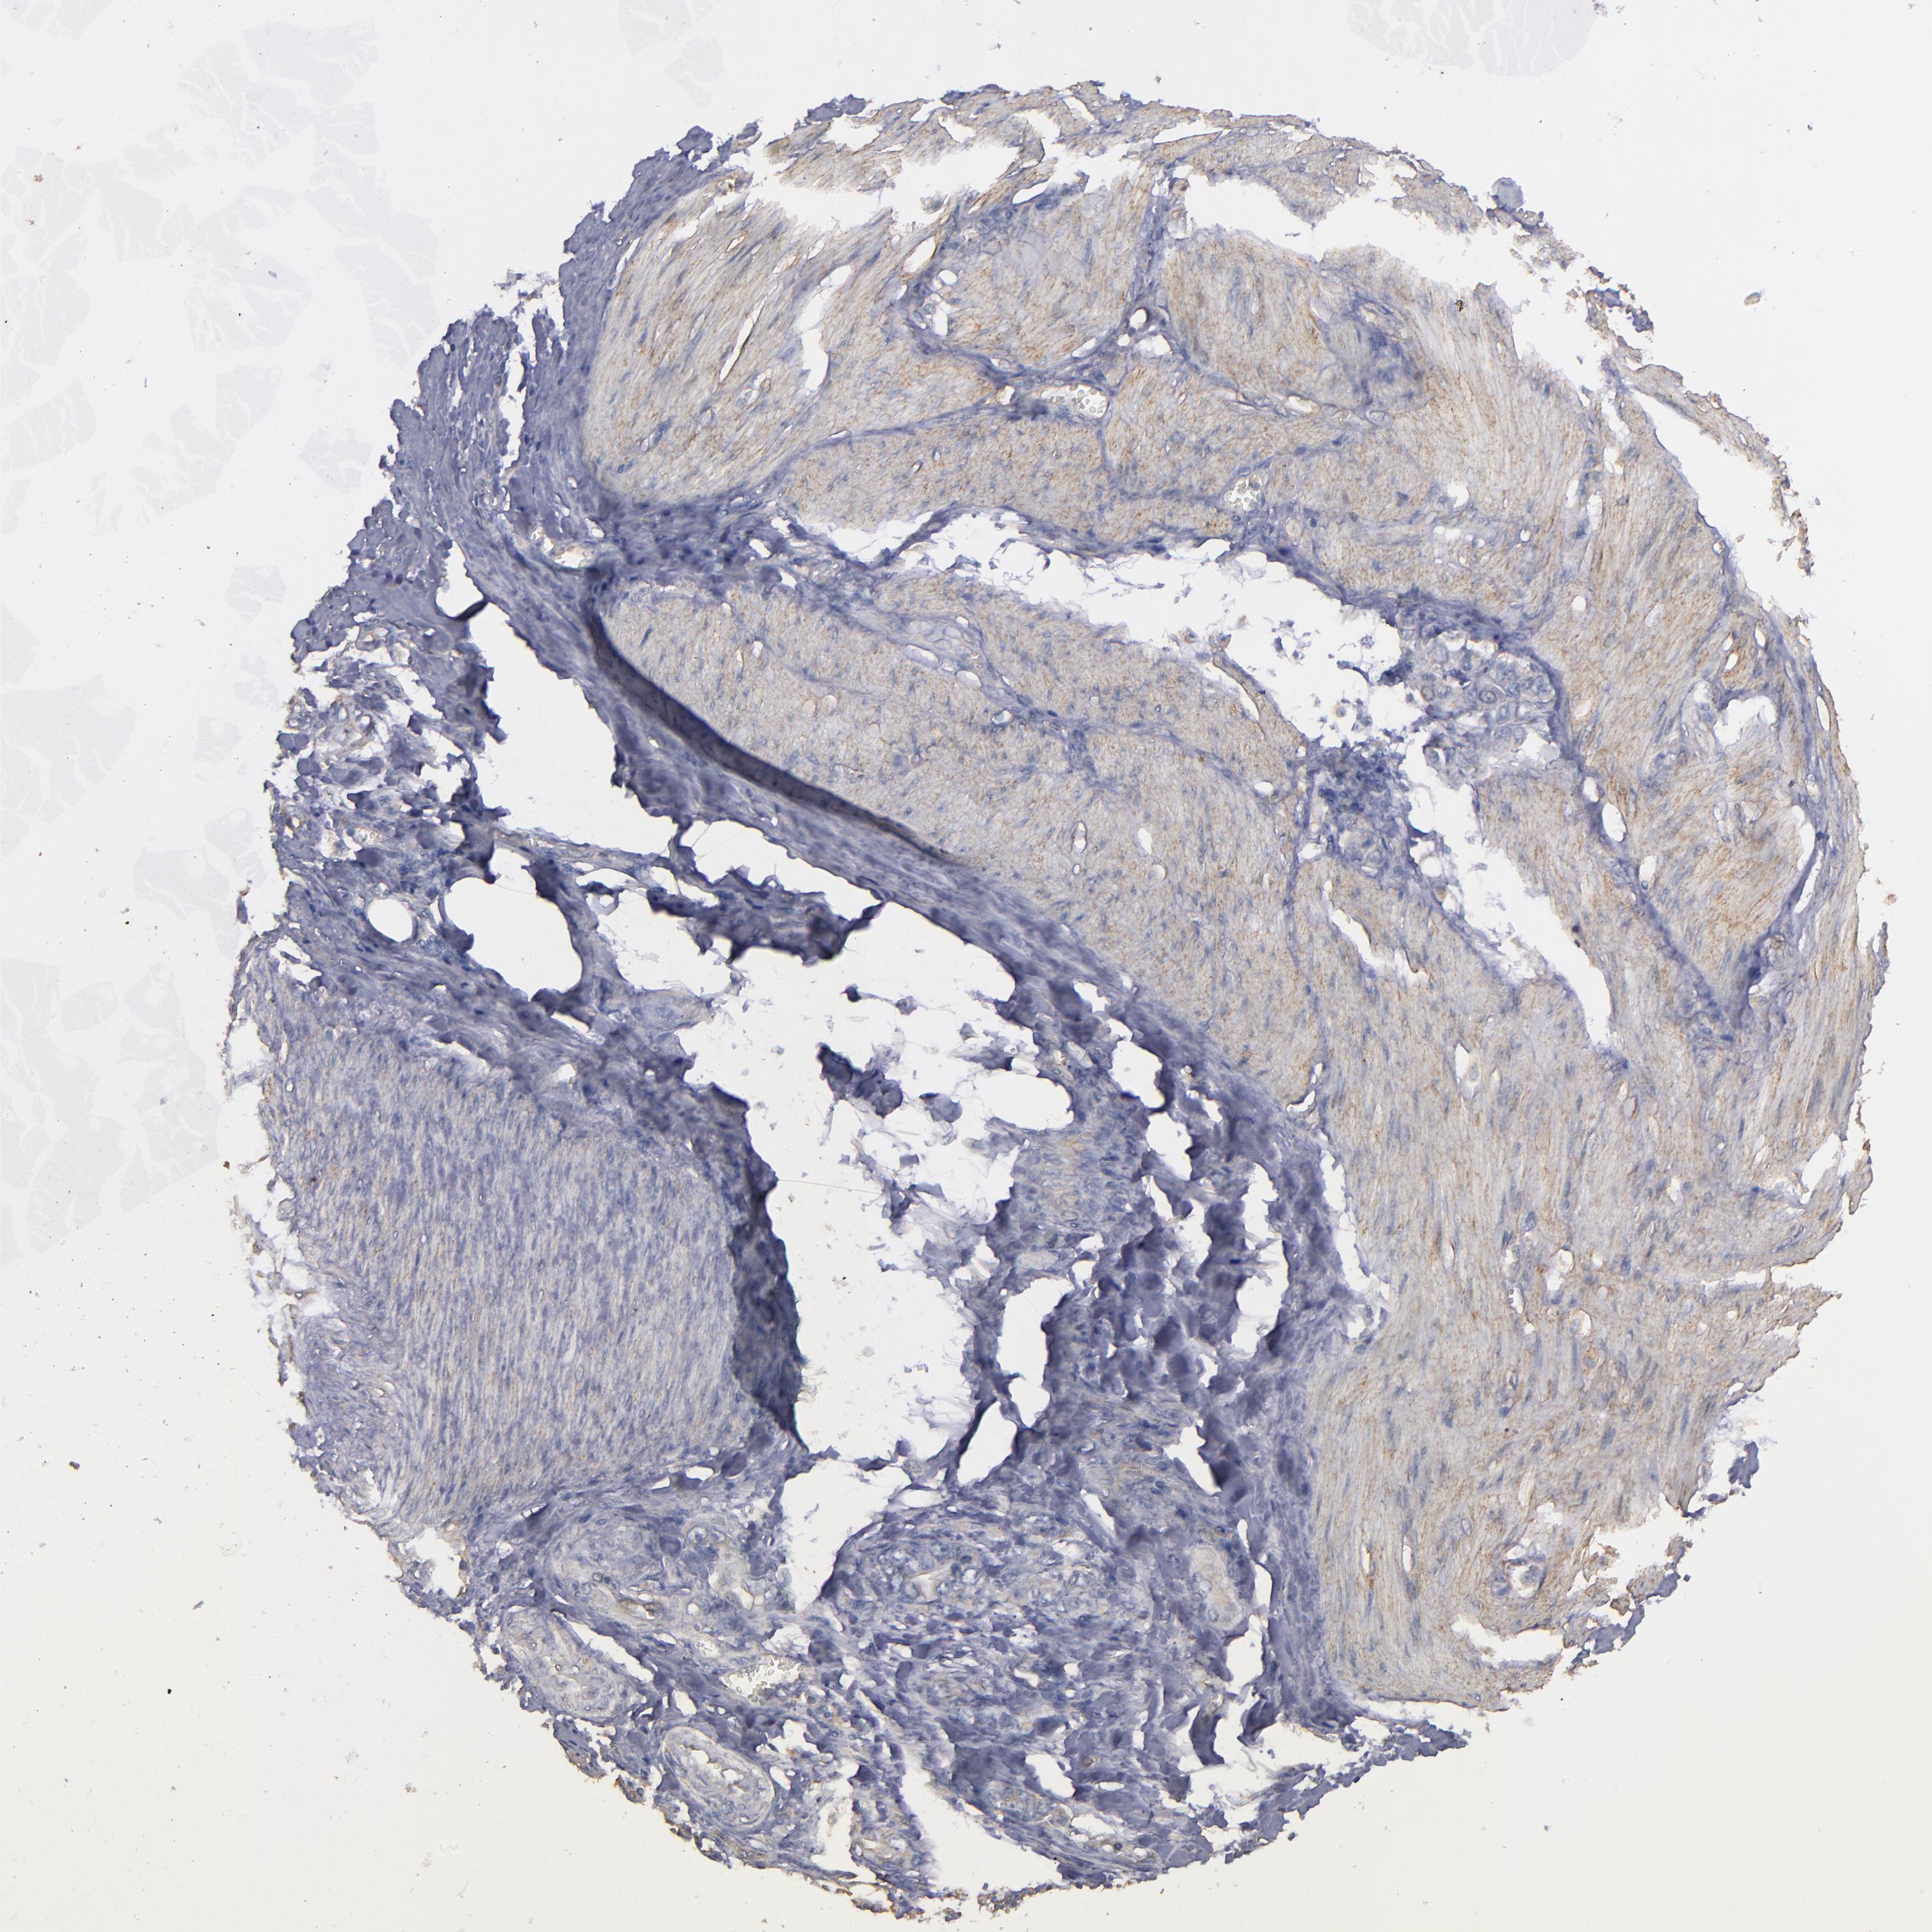

STOMACH CANCER - Protein expressioni

A mouse-over function shows sample information and annotation data. Click on an image to view it in a full screen mode. Samples can be filtered based on level of antibody staining by selecting one or several of the following categories: high, medium, low and not detected. The assay and annotation is described here.

Note that samples used for immunohistochemistry by the Human Protein Atlas do not correspond to samples in the TCGA dataset.

Antibody stainingi

Antibody staining in the annotated cell types in the current human tissue is reported as not detected, low, medium, or high, based on conventional immunohistochemistry profiling in selected tissues. This score is based on the combination of the staining intensity and fraction of stained cells.

Each image is clickable and will lead to virtual microscopy that enables deeper exploration of all samples and also displays staining intensity scores, fraction scores and subcellular localization as well as patient and tissue information for each sample.

Antibody HPA002725

Antibody HPA023885

Antibody CAB000119

Staining

High

Medium

Low

Not detected

Intensity

Strong

Moderate

Weak

Negative

Quantity

>75%

75%-25%

<25%

None

Location

Nuclear

Cytoplasmic/membranous

Cytoplasmic/membranous,nuclear

Adenocarcinoma, NOS